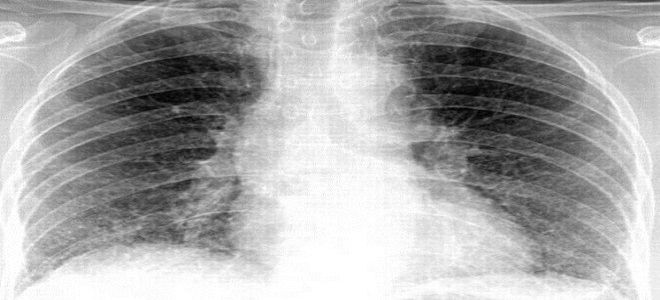

Сегментарная пневмония представляет собой воспалительный процесс в легочной ткани, затрагивающий один или несколько сегментов. Если на рентгеновском снимке выявляется множество таких участков, это указывает на развитие полисегментарной пневмонии. Этот вид заболевания, как правило, имеет бактериальную природу и чаще всего встречается у детей.

Симптоматика данного заболевания напоминает обычное воспаление легких. Признаки полисегментарной пневмонии можно выявить только с помощью рентгенологического исследования (рентгенографию легких или компьютерную томографию). Что касается внешних проявлений, то заболевание начинается резко. Температура тела может достигать 38–39 градусов, также наблюдаются выраженные симптомы интоксикации: